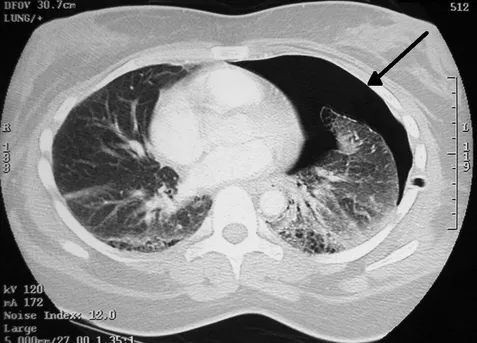

폐기흉 진단 방법

폐기흉이 의심되면 제일 먼저 가슴 엑스레이를 찍습니다. 사진으로 보면 원래는 까맣게 보여야 할 폐 부분이 줄어들고, 공기가 비정상적으로 모인 공간이 보입니다. 조금 더 자세히 보려면 CT 촬영을 하기도 합니다. 만약 응급 상황이라면 초음파로도 빠르게 확인할 수 있습니다.

이러한 검사들을 종합하면 진단 정확도를 높일 수 있으며, 이후 적절한 치료 계획을 세우는 데 중요한 역할을 합니다. 따라서 진단 과정은 단순히 확인이 아닌 치료 방향을 결정하는 핵심 단계입니다.